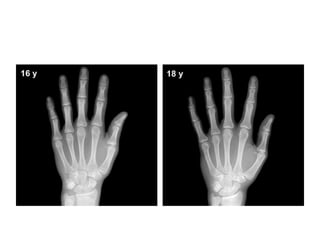

Post-puberty

• Males: 17 years to 19 years of age

• At this stage, all carpals, metacarpals and

phalanges are completely developed, their

physes are closed

• assessments of skeletal maturity are based on

the degree of epiphyseal fusion of the ulna and

radius.

• Depiction, fromleft to

right, of the progressive

degrees of fusion of the

ulna and the radial

epiphyses, which

usually begins at the

center of the physis

Post-puberty • Females:15 years to 17 years of age • Males: 17 years to 19 years of age • At this stage, all carpals, metacarpals and phalanges are completely developed, their physes are closed • assessments of skeletal maturity are based on the degree of epiphyseal fusion of the ulna and radius.

• Depiction, fromleftto right, of the progressive degrees of fusion of the ulna and the radial epiphyses, which usually begins at the center of the physis